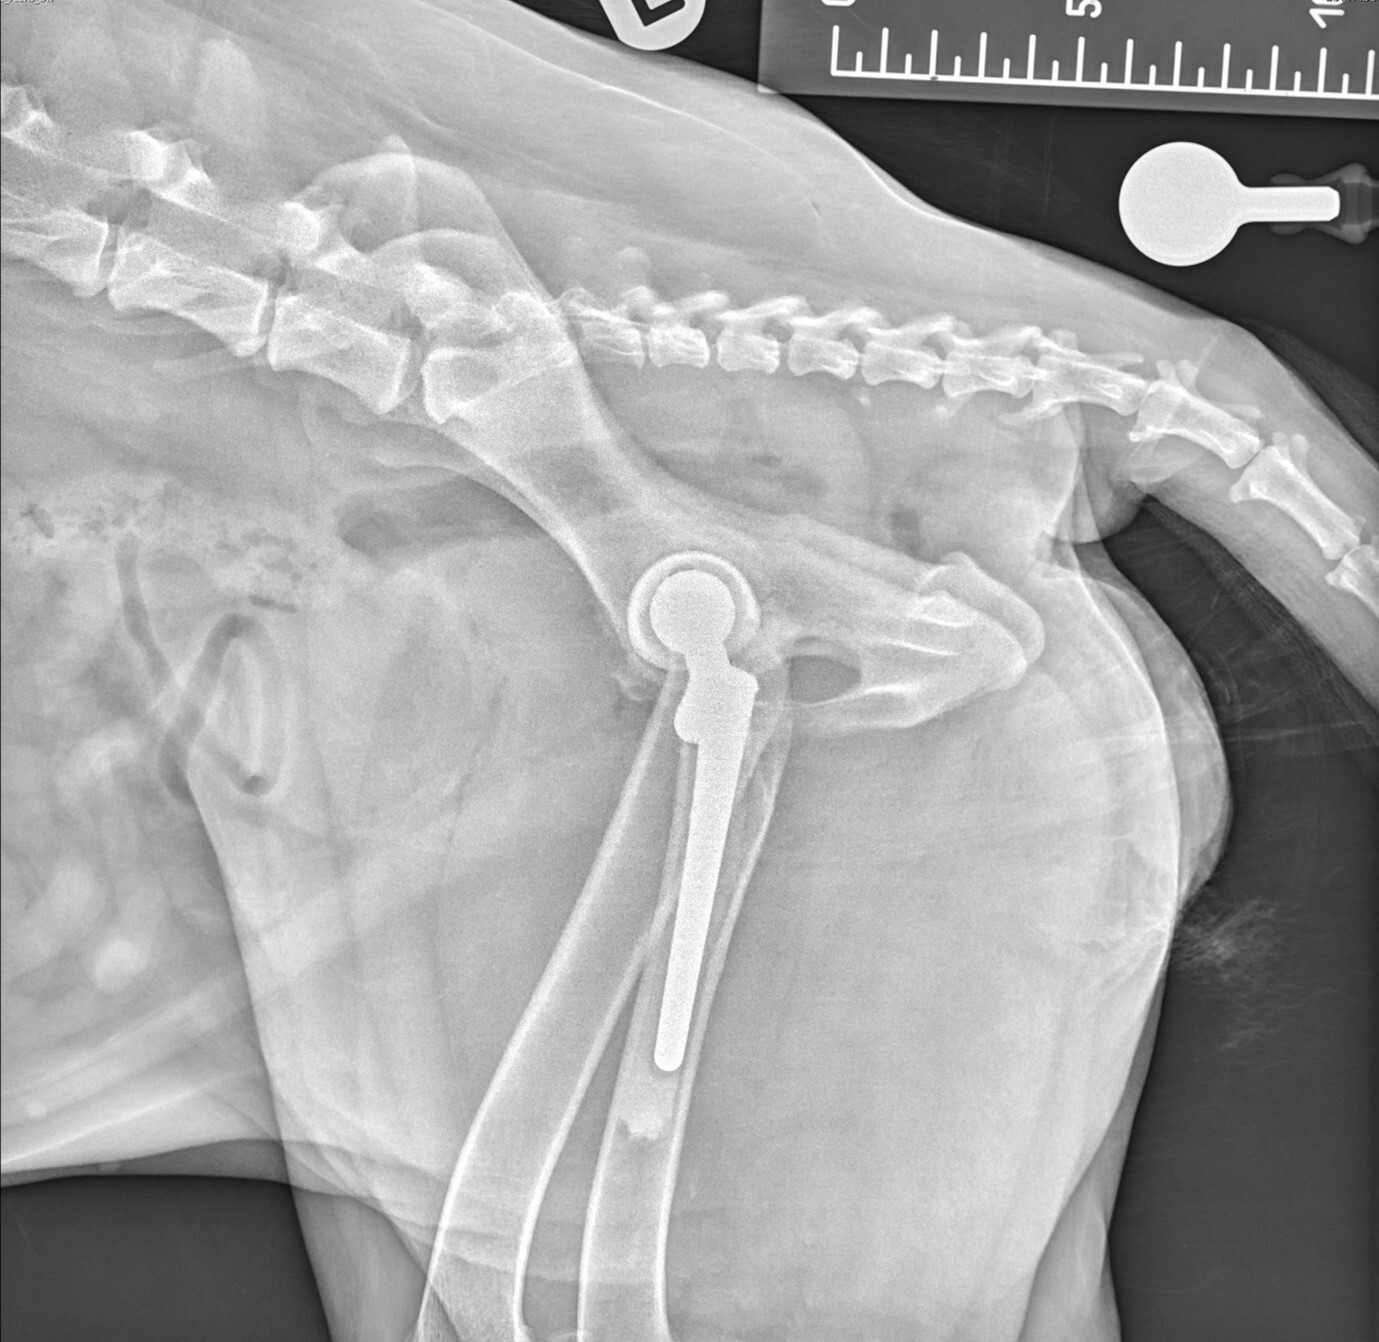

The final metal femoral head was placed and hip reduction was achieved with a good range of motion and stability. Standard layered soft tissue closure was performed after generous saline lavage of the surgical site. Radiographs were then taken post-operatively to assess the implant placement, which was correct, and a good cement mantle could also be seen (Figure 2A and 2B).